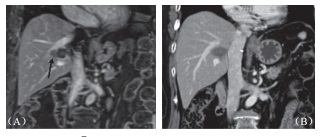

本研究中所治疗之肿瘤均贴近血管,随访期间也未见血管狭窄或栓塞(图3),影像上也未见受波及胆管进一步扩张或狭窄,只有一位在第9个月出现局部复发的病患,出现轻微胆管扩张,但无胆红素上升之异常。在12个贴近胆囊及15个贴近肠胃壁的肿瘤消融之后,仅有一位(8.3%)在术后超声中出现无症状的胆囊壁水肿,而在1个月后改善,无任何肠胃道受损或消化受影响的迹象。两人术前曾放置胆管内塑料质支架,术后移除时经检视支架无损伤,移除后也不再黄疸。

图3 55 岁男性肝癌病患在接受射频消融后右肝静脉及右侧门脉旁复发,(A)2cm×1.5cm 大小肿瘤(箭头处)直接侵犯右肝静脉;(B)消融后 6 个月血管内及血管侧肿瘤消失,仅余前度射频消融遗迹,邻近血管无损伤